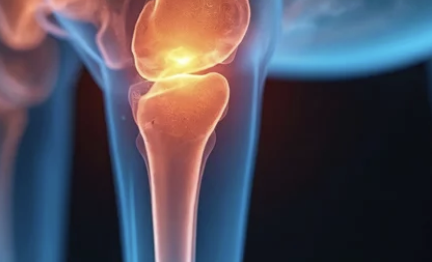

1️⃣ 슬개골 탈구란 무엇일까?

강아지의 무릎(슬개골)은 대퇴골 홈 안에 위치해 있어

다리 움직임을 안정적으로 도와주는 역할을 합니다.

하지만 이 슬개골이 제자리를 벗어나면,

관절이 어긋나면서 통증과 보행 이상이 생기죠.

무릎뼈가 옆으로 ‘툭’ 빠지는 상태예요.